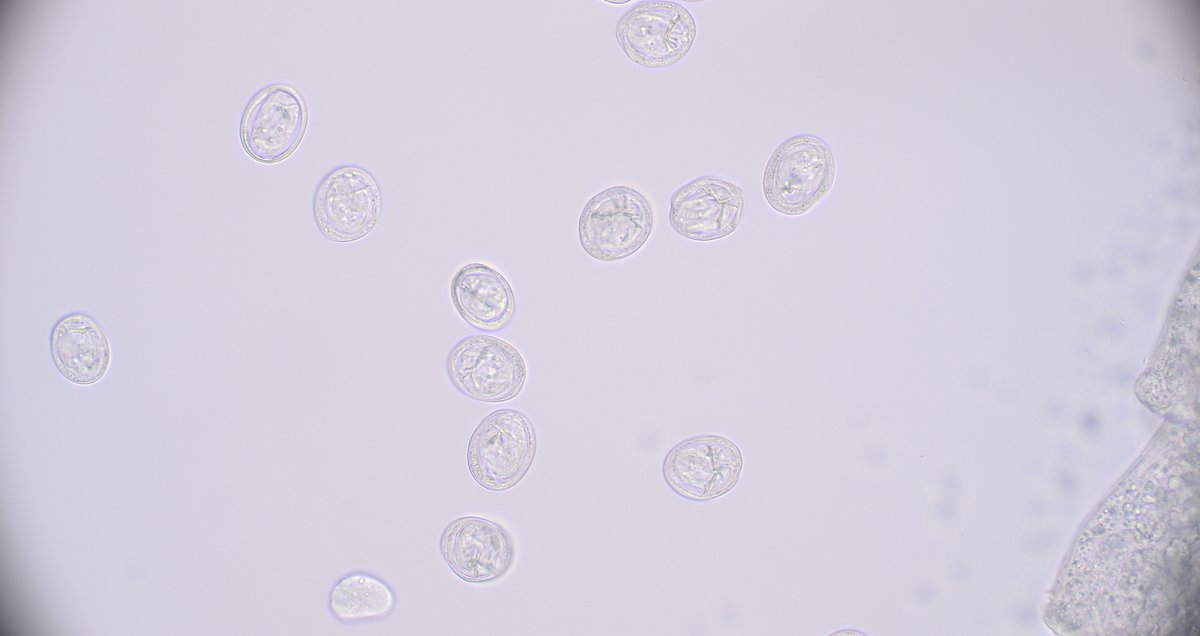

The #Parasite case 778 is now up: parasitewonders.blogspot.com/2025/06/case-o… - colon biopsy from a patient with abdominal pain and diarrhea. Objects seen are 20 microns. What is your diagnosis? Answer later this week! #mayopath #pathology #PathBugs

The #Parasite case 778 is now up: parasitewonders.blogspot.com/2025/06/case-o… - colon biopsy from a patient with abdominal pain and diarrhea. Objects seen are 20 microns. What is your diagnosis?

Answer later this week!

#mayopath #pathology #PathBugs